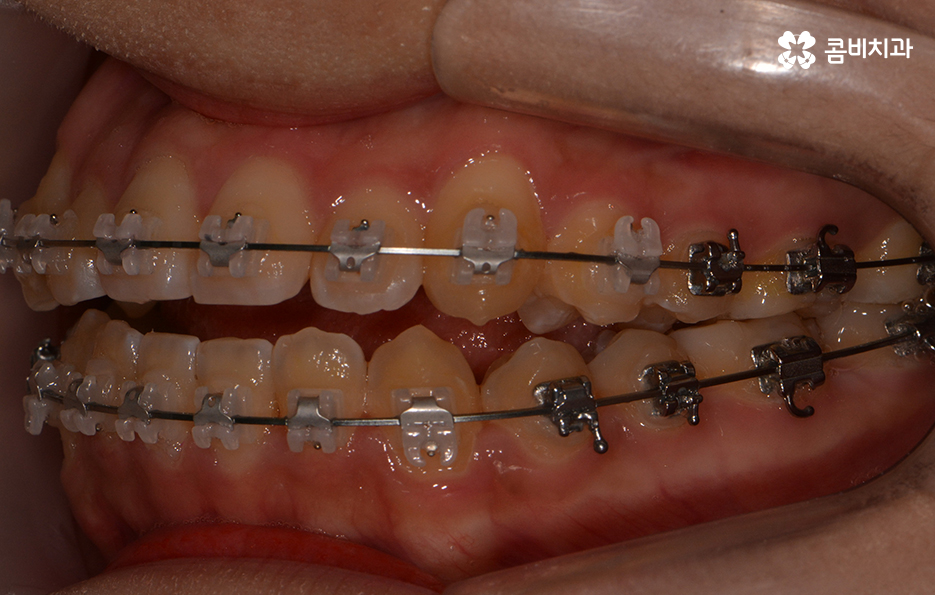

위 환자분의 경우에는 비발치로 송곳니 덧니 교정이

진행된 사례이며 전체 진료 기간은 약 1년 6개월가량이 소요되었습니다.

클리피씨 교정을 통해서 덧니가 개선되고 있는 경과

클리피씨 교정의 경우에는 일반적인 교정 방법에 비해서

진료 기간을 단축시킬 수 있다는 장점이 있는데

자가 결찰 장치로 서서히 치아를 지속적으로 이동시켜서

초기 통증은 줄이고 교정 기간의 단축이 가능합니다.

또한 교정 장치의 재질이 세라믹이기 때문에

심미적이라는 장점이 있으며 철사로 인한 찔림이

클리피씨 교정의 또 한 가지 장점은 주기적으로

치과를 내원해야 하는 횟수를 줄일 수 있다는 점입니다.

클립형태로 와이어를 고정시키기 때문에 철사로 와이어를 고정하는

일반 교정 장치에 비해 치아 이동이 빠르고, 와이어를 조정하는데 용이하여

일반 장치에 비해 치아가 빨리 펴지게 됩니다. 이로인해 주기적으로 치아에